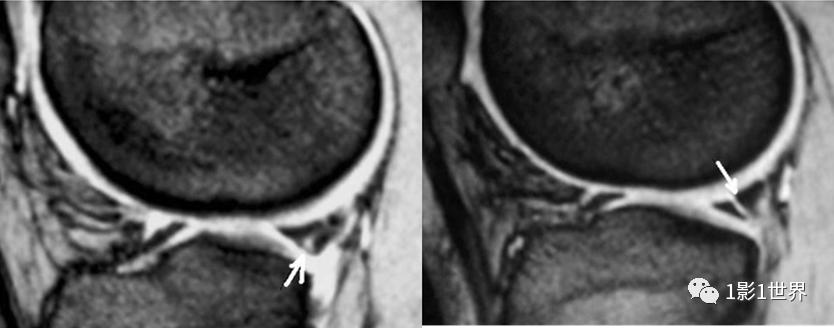

磁共振显示半月板损伤、韧带或肌腱损伤非常清晰